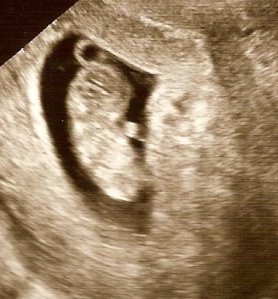

Peanut had his/her first close up last week. This was a monumental day for me since those five weeks that just CRAWLED by were filled with fears, anxieties, and horror stories about miscarriages, accidents, and omglookateverythingthatcouldgowrong. I wanted to see the ultrasound so bad so I could just be RID of all those ugly feelings. I didn’t sleep a wink the night before and was in tears the next morning, so worried of what I might find in the ultrasound.

The good part: As I sat in that chair and watched my baby…OUR baby!… flail about on that screen, my heart melted. He was really in there. He had a face and arms and legs and he was moving! A lot! It was mesmerizing to watch because I don’t feel a thing. I haven’t done anything to focus any energy on my belly so that a person could begin growing. But yet there he was, dancing away as we watched, his heart beating so fast. And I felt relief that he was ok. That’s just all I wanted. To know he was fine.